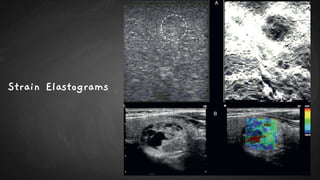

Strain Elastograms

STRAIN ELASTOGRAPHY

● Advantages

- First elastography technique developed; most widely used and validated.

- Does not require a complex software.

● Limitations

- Operator dependent.

- Absence of a specific quantification.

- Limited to superficial organs; i.e. breast, thyroid.